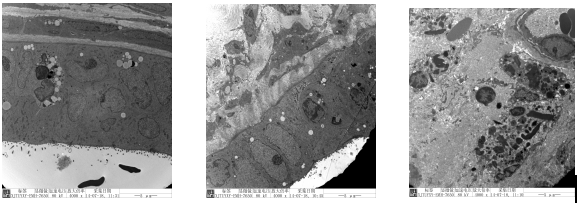

宫瘤消胶囊中、高剂量组:上皮细胞排列紊乱,部分细胞呈肿胀、坏死、凋亡的形态学改变,细胞游离面微绒毛减少或消失;胞核形状不规则,核内染色质轻度凝集、边集,核仁边移;线粒体肿胀,电子密度降低基底膜结构不完整,相邻细胞间连接结构消失,细胞间可见数量较多的巨噬细胞浸入。

(空白组 4000×) (模型组4000×)(桂枝茯苓胶囊组4000×)

(小剂量组 4000×)(中剂量组 4000×) (大剂量组 4000×)